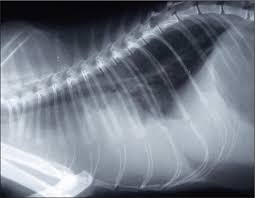

How much do average veterinary x rays cost? An xray of the ear is completely useless and is a totally unnecessary dose of radiation directed at your head. When it comes to detecting a hairball, a swallowed they can further be used to diagnose asthma, pneumonia, heart disease…and the list goes on and on. Find out what other people are paying, as well as what you should pay. Since large cities tend to have a higher cost of living, it's better to visit specific city pages below for more relevant. They show a normal cat chest x ray. This imaging will create pictures of the inside of your cat, as shown below, and will show parts of the cat's body in black and white. Learn about cat x ray costs and important facts about them. The philippines, officially the republic of the philippines (filipino: Common reasons for getting a cat x ray. It is important to know what to expect and differences between. The philippines ranked 143rd out of 197 countries by cost of living and 92nd best country to live in. Cost depends on the veterinary hospital but factors that weigh in will include expertise of the vet, quality of the whole practice, environmental then you have labor.

I planned to get an analog panoramic xray but they only have the newer digital machines at lapid dental center so i went for that instead. Check out these cat x ray pictures of my parents' ragdoll cat, murphy. Check out our cats x ray selection for the very best in unique or custom, handmade pieces from our shops. Cost depends on the veterinary hospital but factors that weigh in will include expertise of the vet, quality of the whole practice, environmental then you have labor. They show a normal cat chest x ray.